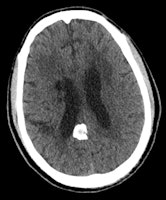

Macroscopic calcifications are present in meningiomas in up to 60% of cases, the pattern of which may range from diffuse, rim, or sand-like to focal or even globular. Calcified meningiomas can be associated with focal thickening of the overlying skull bones or with dilatation of the adjacent air-containing sinus of the skull base, they stated.

"Various imaging findings have been found to suggest an extra-axial localization of brain lesions such as buckling of adjacent white matter, expansion of the ipsilateral subarachnoid space, presence of bony reactions and the 'dural tail' sign," Celzo et al noted. "The most common extra-axial etiologies of brain stones include meningiomas, dural osteomas, calcifying tumors (e.g. craniopharyngiomas) as well as exaggerated physiological calcifications."